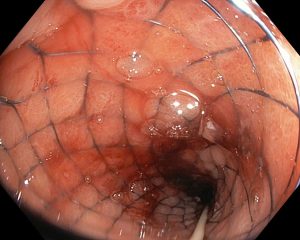

Hình ảnh trực tràng đã được đặt stent thành công